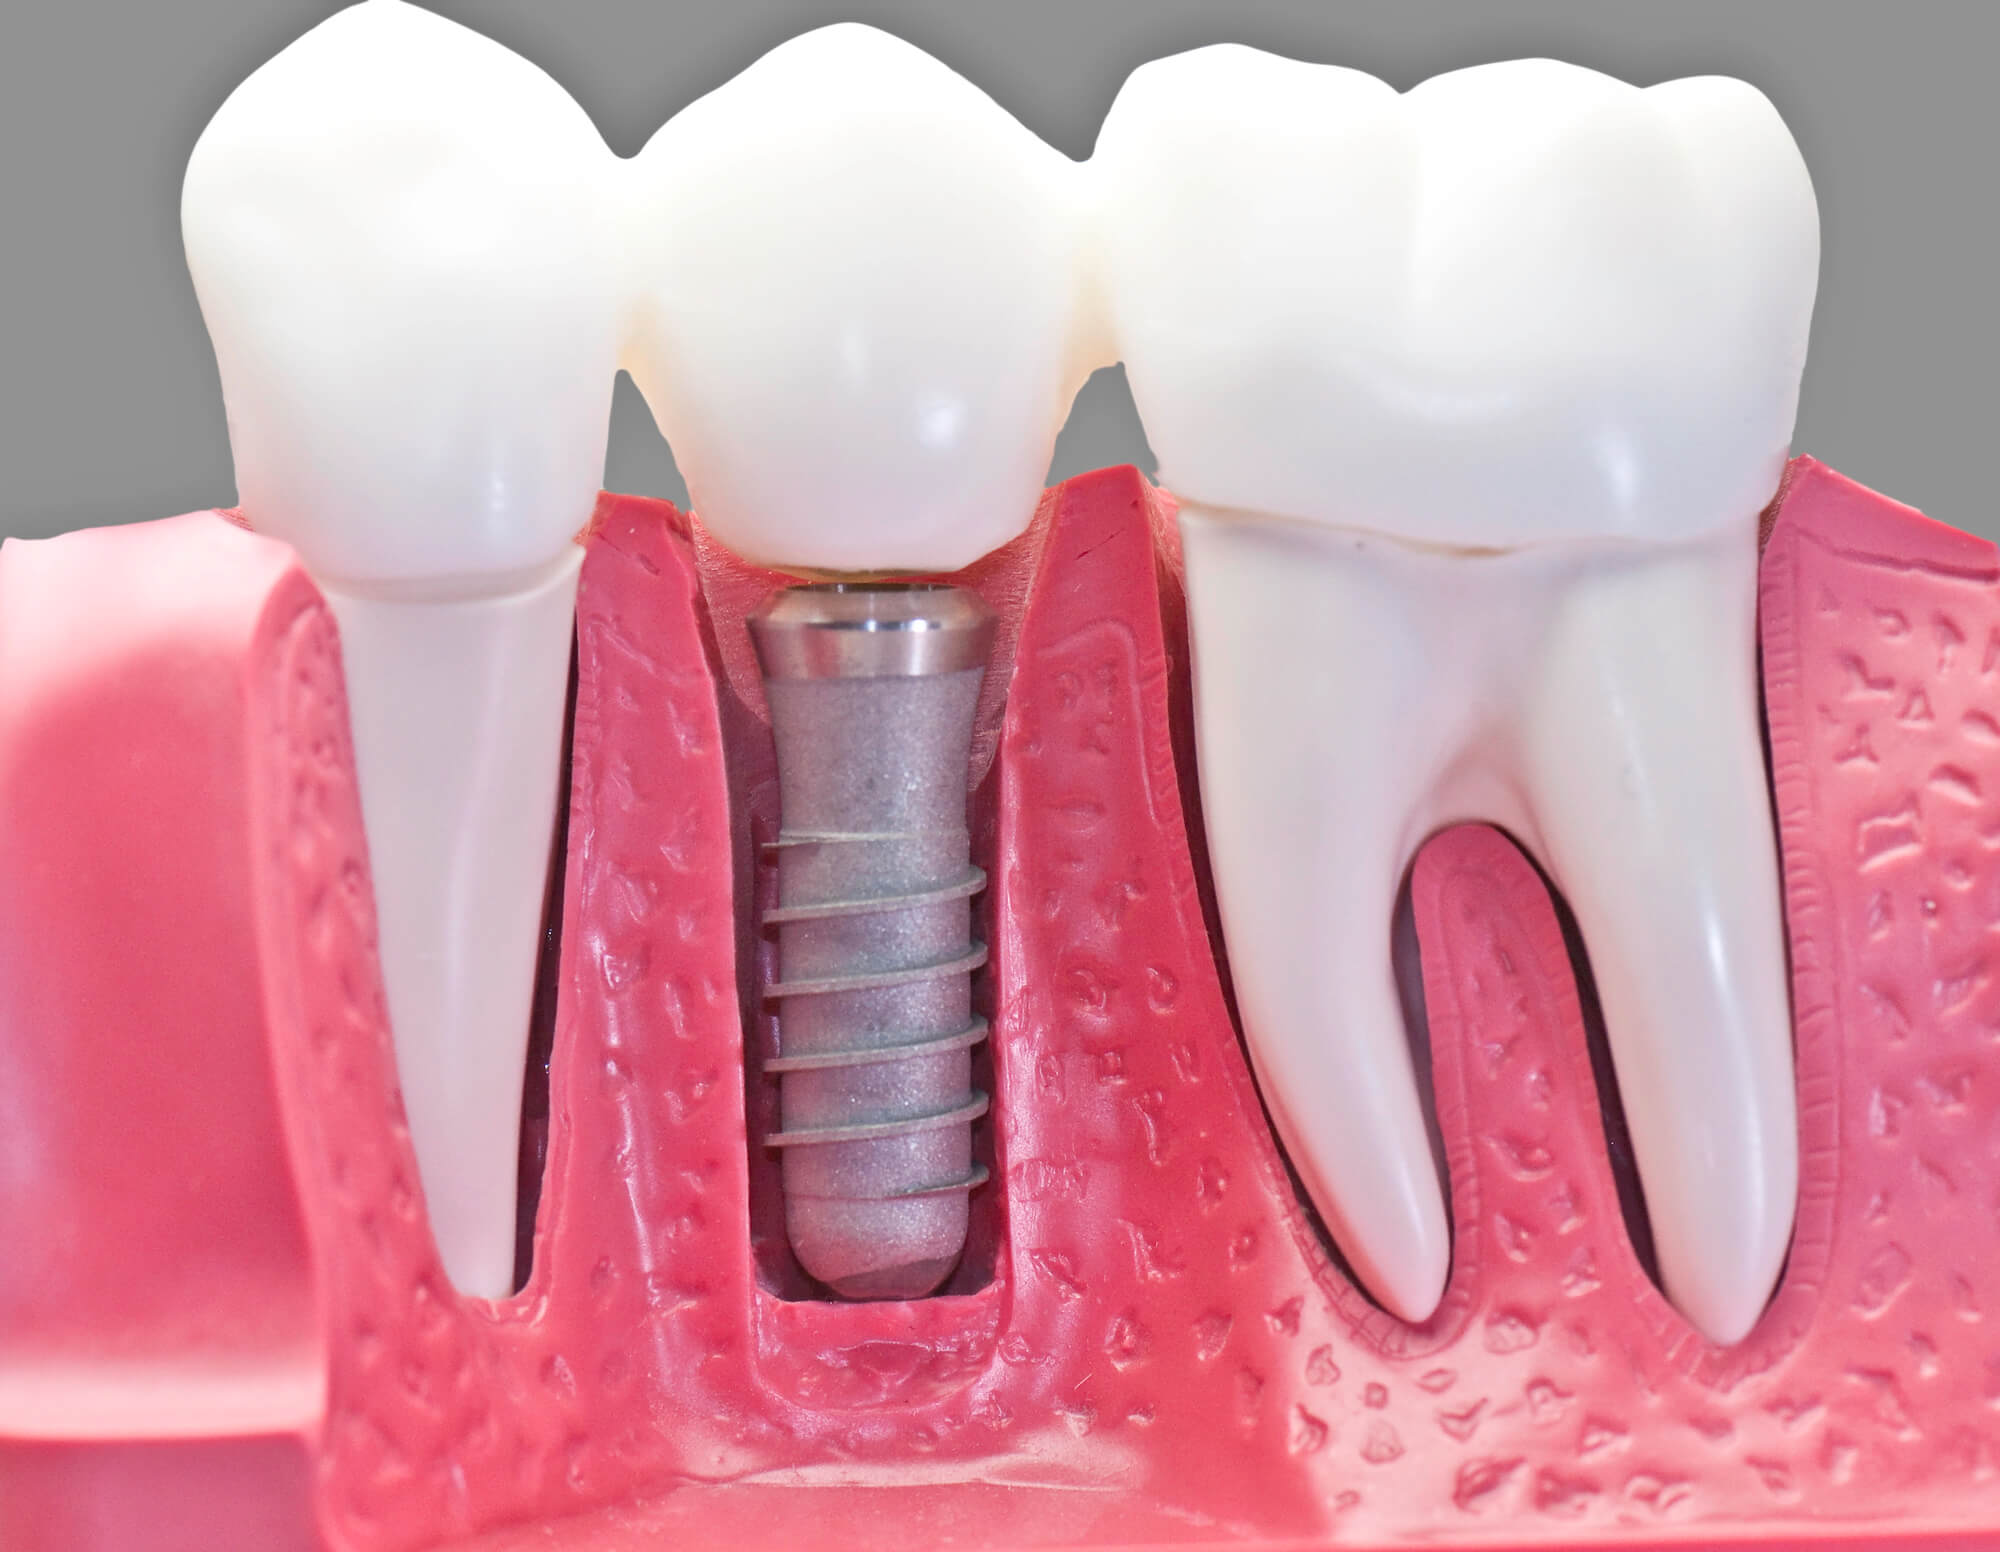

Dental implants in Coral Gables are an effective and long-lasting dental restoration. Unlike bridges that rely on the surrounding teeth for support, implants imitate the structure of a natural tooth, with a titanium screw that attaches to your jawbone to ensure a stable prosthetic.

To prevent this, dental professionals recommend getting dental implants. Implants are inserted into the jawbone, providing the necessary stimulation to keep it healthy. Moreover, the customized crown placed on top keeps the surrounding teeth from shifting, ensuring your smile stays well-aligned and straight.